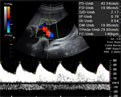

Ecografía 4D del tercer trimestre: Cara y cuerpo de un feto

Ecografía de una bebé moviéndose en el tercer trimestre de embarazo. Lo normal a estas alturas de la gestación es captar sólo la cabeza, la cara o una parte del feto. En esta imagen 4D podemos ver además al niño moviendo sus extremidades con fuerza.

Ecografía 4D de la cara y el cuerpo de un feto moviéndose

Esta ecografía 4D, realizada en el tercer trimestre de embarazo, es especialmente interesante porque logra captar la mayor parte del cuerpo del bebé. Además, le sorprende en pleno movimiento de brazos y piernas. Cabe destacar la nitidez con la que se aprecia el brazo derecho del bebé, en el que se notan hasta los huesos de la citada extremidad.